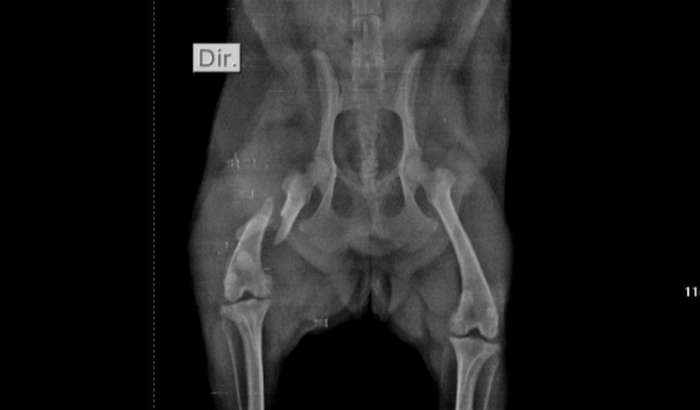

Hoje estou aqui pedindo a ajuda de vocês para salvar a minha cachorrinha Nina. Ela foi atropelada recentemente e, infelizmente, quebrou o fêmur direito. Precisamos de apoio para arcar com os custos da cirurgia que é 2,500.00$ para que ela possa se recuperar e voltar a andar com saúde e alegria.